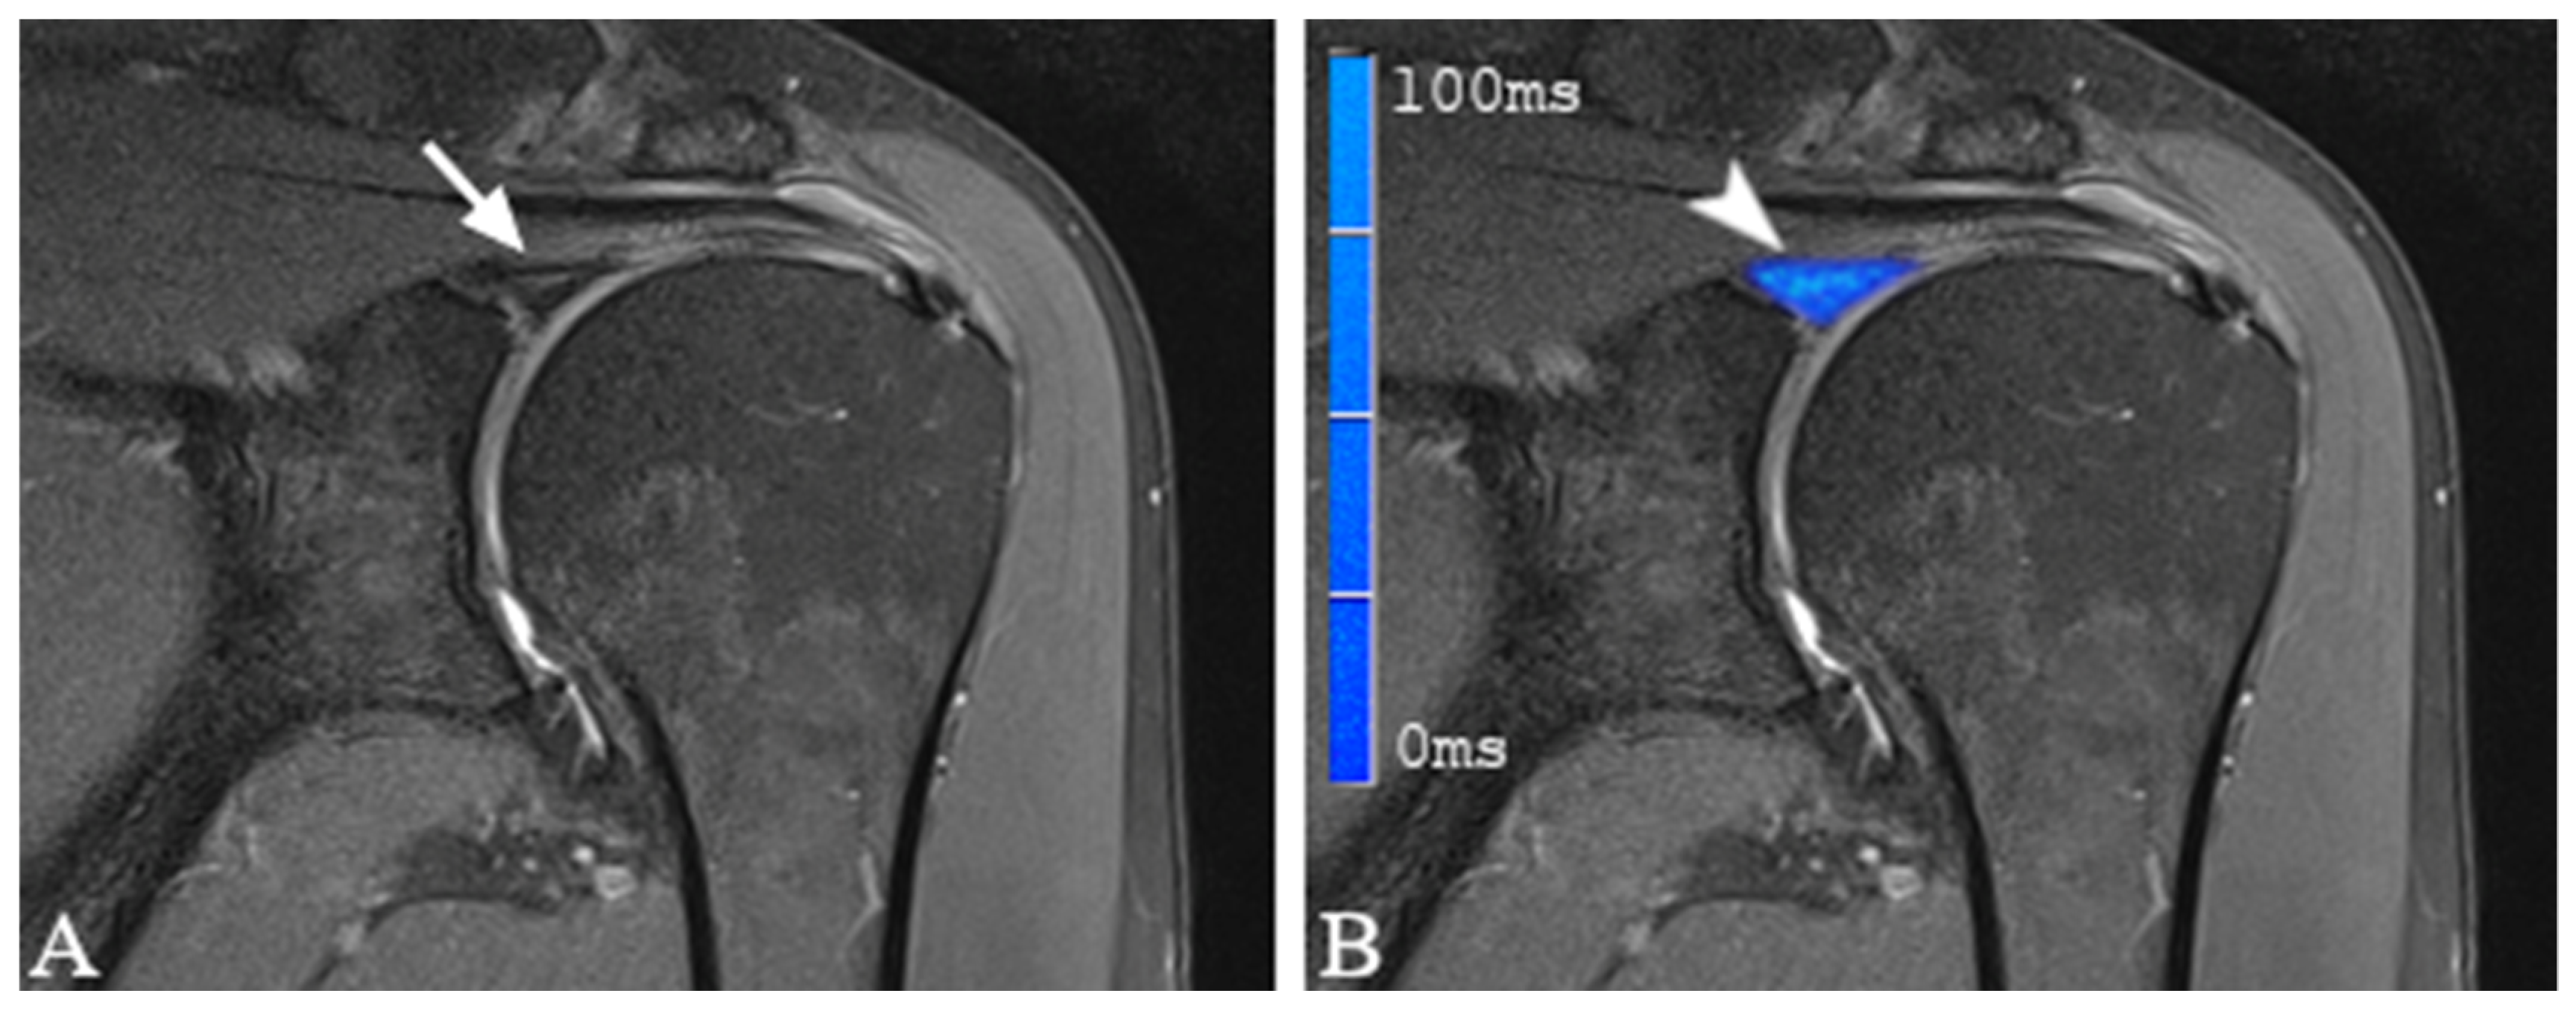

2.3. MRI Protocol and T2 Mapping

2.4. Image Analysis and Definition of SLAP Lesions